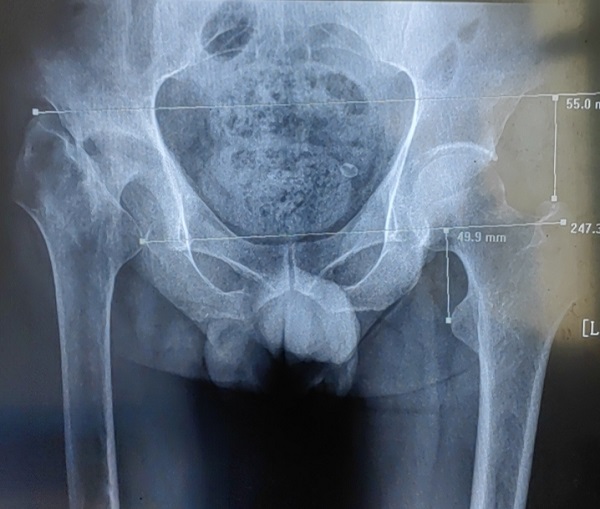

股骨头坏死的原因多种多样,其中最被公认的是髋关节骨折创伤后骨不连及股骨头坏死。一旦发生坏死,几乎为不可逆性发展,发展到一定程度将严重影响患者工作和生活。 李师傅今年54岁,11年前因外伤致股骨颈骨折在外院...